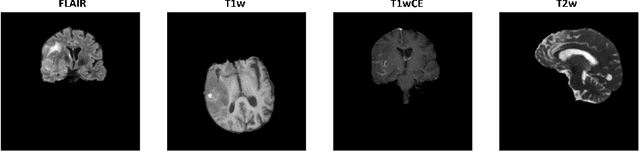

Abstract:Glioblastoma is a common brain malignancy that tends to occur in older adults and is almost always lethal. The effectiveness of chemotherapy, being the standard treatment for most cancer types, can be improved if a particular genetic sequence in the tumor known as MGMT promoter is methylated. However, to identify the state of the MGMT promoter, the conventional approach is to perform a biopsy for genetic analysis, which is time and effort consuming. A couple of recent publications proposed a connection between the MGMT promoter state and the MRI scans of the tumor and hence suggested the use of deep learning models for this purpose. Therefore, in this work, we use one of the most extensive datasets, BraTS 2021, to study the potency of employing deep learning solutions, including 2D and 3D CNN models and vision transformers. After conducting a thorough analysis of the models' performance, we concluded that there seems to be no connection between the MRI scans and the state of the MGMT promoter.